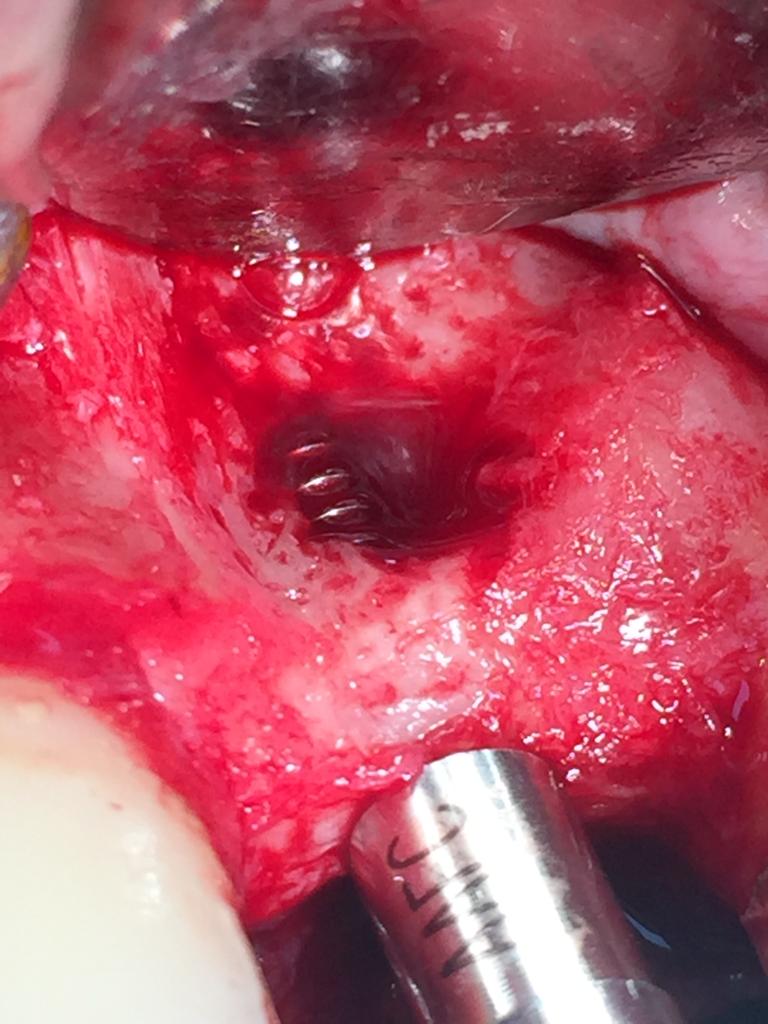

PRELEVEMENT RAMIQUE